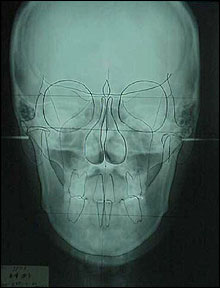

P-A Cephalogram

CEPHALOMETRIC TRACINGS

SN at S

ANS-PNS at ANS

Go-Gn at Me |

Z-angle Change